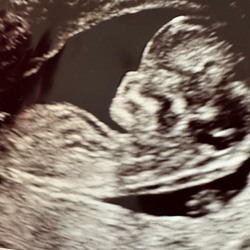

Nub denk ik ook een 🩵 maar ik kan het niet helemaal goed zien.

Laat je Nub niet door Chatgpt doen maar doe hem zelf via de gratis website nubcheck. Of vraag aan chatgpt of hij wil aangeven welke lijnen hij gebruikt. Bij mij zat hij 9/10 keer niet eens in de buurt van de baby.